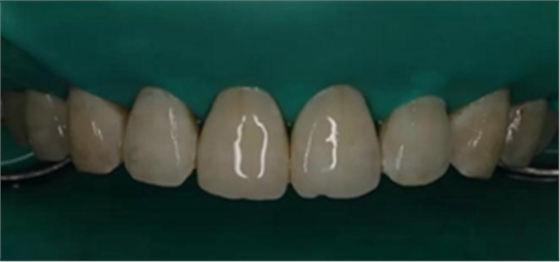

6、去除橡皮章拋光

拋光第一步 用矽粒子去除唇腭側多余樹脂,平整牙面,后使用高級樹脂拋光套裝逐步拋光。這一步目的在于高度拋光樹脂和釉質復合牙面。

術后顯示,滲透樹脂恢復了天然牙釉質的折光率(天然通透牙釉質折光率1.62滲透樹脂折光率是1.52)顯的很自然,很有光澤。完全是天然牙質的顏色。

(下圖是拋光完成)

治療完成的上頜牙齒和未治療的下頜牙齒形成明顯對比。

治療前和治療后的對比,患者很高興很滿意。